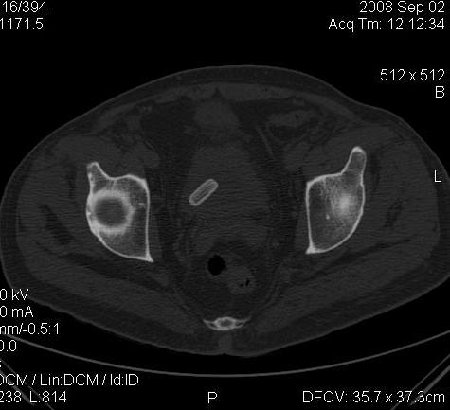

КТ Малого таза.

Что в мочевом пузыре? :?: ;)

Я тоже так думал! Урологи выполнили цистоскопию, оказалось камень, такой причудливой формы.